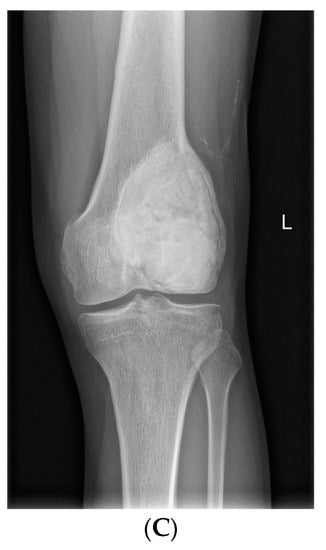

- Van Langevelde, K.; McCarthy, C.L. Radiological findings of denosumab treatment for giant cell tumours of bone. Skelet. Radiol. 2020, 49, 1345–1358. [Google Scholar] [CrossRef] [PubMed]

- Oguro, S.; Okuda, S.; Sugiura, H.; Matsumoto, S.; Sasaki, A.; Susa, M.; Morioka, H.; Jinzaki, M. Giant Cell Tumors of the Bone: Changes in Image Features after Denosumab Administration. Magn. Reson. Med. Sci. 2018, 17, 325–330. [Google Scholar] [CrossRef]

- Hakozaki, M.; Tajino, T.; Yamada, H.; Hasegawa, O.; Tasaki, K.; Watanabe, K.; Konno, S. Radiological and pathological characteristics of giant cell tumor of bone treated with denosumab. Diagn. Pathol. 2014, 9, 111. [Google Scholar] [CrossRef]

- Branstetter, D.G.; Nelson, S.D.; Manivel, J.C.; Blay, J.-Y.; Chawla, S.; Thomas, D.; Jun, S.; Jacobs, I. Denosumab Induces Tumor Reduction and Bone Formation in Patients with Giant-Cell Tumor of Bone. Clin. Cancer Res. 2012, 18, 4415–4424. [Google Scholar] [CrossRef] [PubMed]